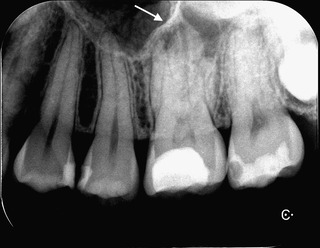

口蓋側にフィステルの様なニキビの様なものが見られたので、デンタルを撮影。

充填物がかなり歯髄に近く、(虫歯が残っているとかはないですが)

おそらく歯髄壊死を起こしてしまって根尖部に膿が溜まっていたもよう。

根尖部に透過像(黒い部分)が見られました。 (正常だと白い)